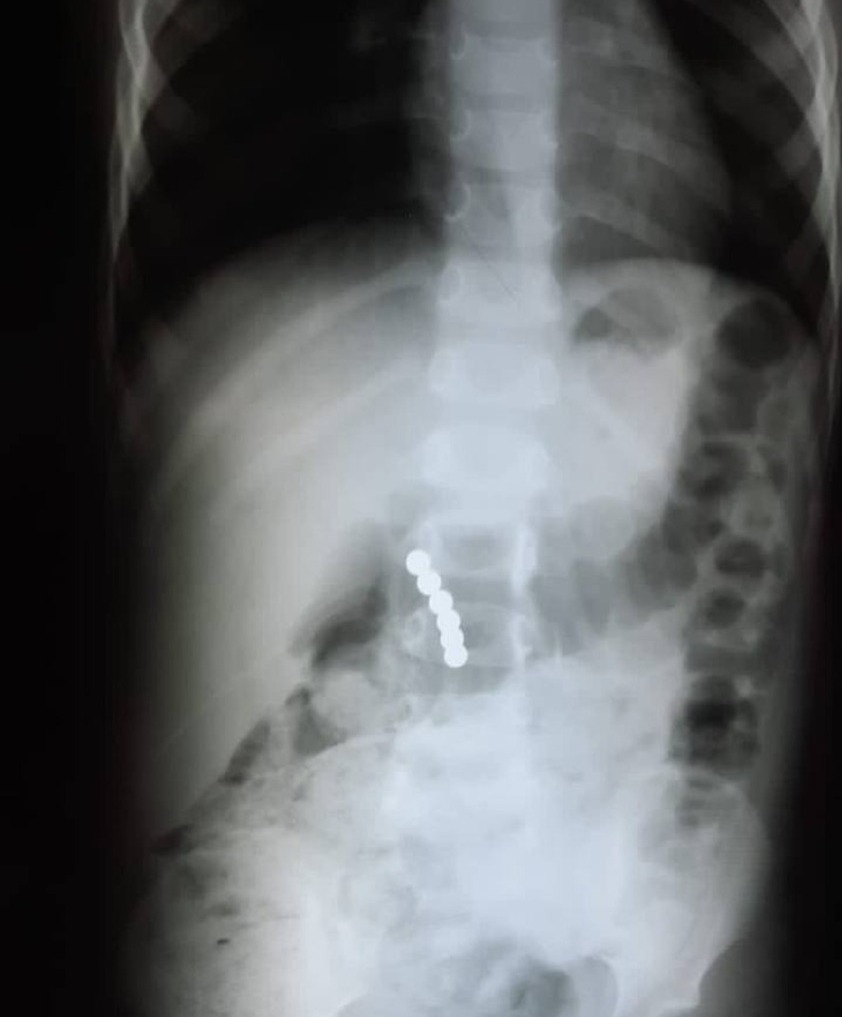

В апреле в уфимскую детскую клиническую больницу № 17 поступил семилетний мальчик, который проглотил шарики от магнитного конструктора. При рентгенографии желудочно-кишечного тракта были выявлены две тени округлой формы, соединенные между собой диаметром 5 мм, предположительно, в куполе слепой кишки. Хирургическая бригада провела экстренную операцию: магнитные шарики были успешно извлечены. Врачи использовали менее травматичный оперативный метод: не вскрывая просвет кишечника, при помощи пальцев переместили инородные тела в червеобразный отросток и провели аппендэктомию. Если бы магниты оказались в разных петлях кишечника, то произошла бы перфорация кишечника и каловый перитонит, что очень опасно для жизни.